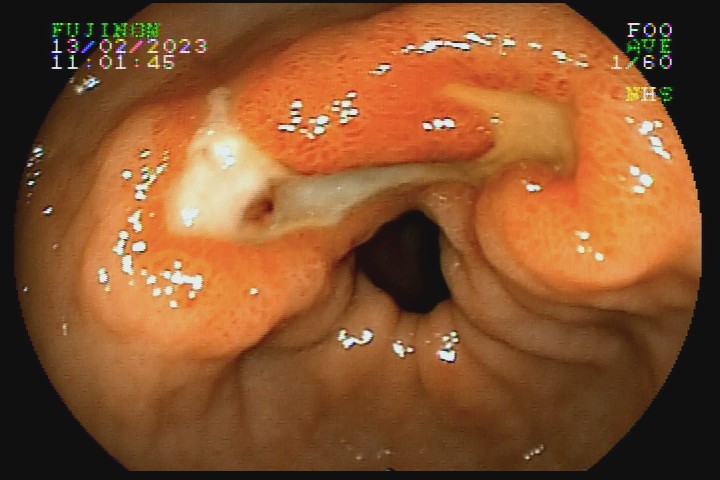

• A1 - base recoberta por espessa camada de fibrina, com pontos de hematina ou restos necróticos; borda bem definida, escavada, tumefeita, enantematosa, geralmente sem convergência de pregas.

• A2 - base recoberta por espessa camada de fibrina clara e limpa; formato arredondado ou oval, com borda bem definida, regular, menos tumefeita, com discreta convergência de pregas para a lesão.